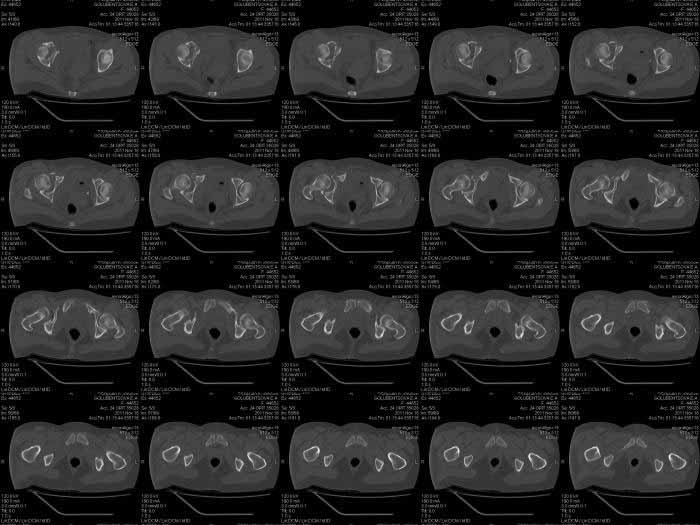

Кт снимки

КТ срезы помогают увидеть мелкие фрагменты и маргинальную импакцию, но на ваших мелких срезах трудно увидеть повреждение боковой массы крестца? Классифицировать перелом вертлужной впадины по Летурнелю все таки привычнее на косых Judet снимках.

Некоторые переломы вертлужной впадины между собой трудно отличаются, и надо проводить дифференциальную диагностику переломов: Т-образного, двух колонного и комбинации поперечного с переломом задней стенки (Associate

Transverse &Posterior Wall). Отсутствие вовлечения крыла подвздошной кости при двухколонном и наличие перелома в седалищной кости говорит о

Т-образном переломе.